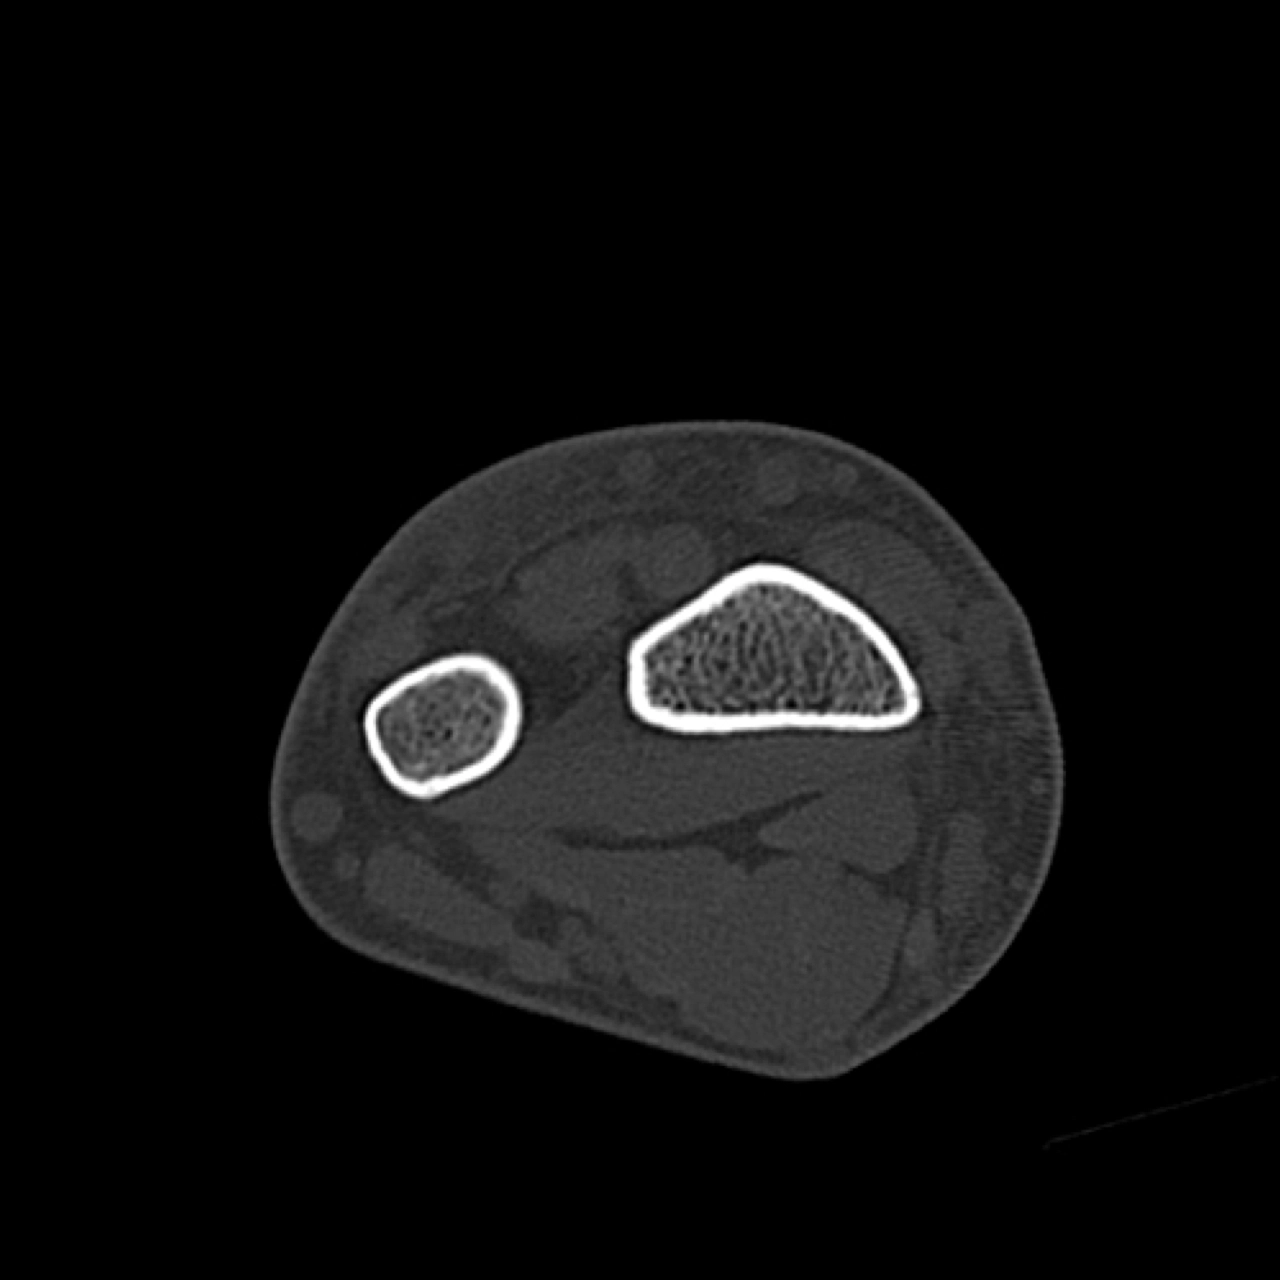

CT

Trả phí

CT khớp vai

16/03/2026

CT xương cổ tay